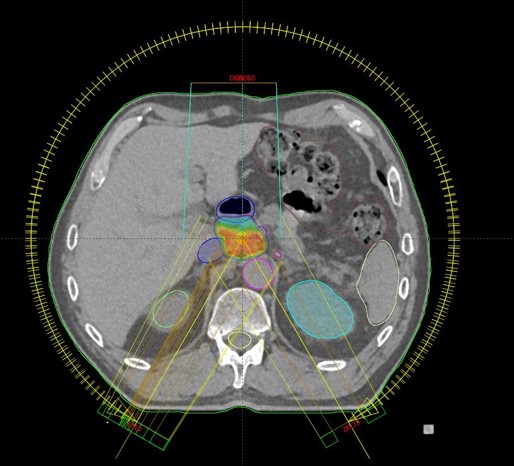

SBRT ppt recidivum locoregionalis tm oesophagei (30.09.2020. - 07.10.2020., TD 35 Gy/5 fr.)

SBRT lymphonodi intraabdominalis (22.11. - 26.11.2021.)

SABR meta hepatis (16.03.-24.03.2023.)

Rezultat – 19 mjeseci nakon RK

Potpuni nestanak tretiranog limfnog čvora